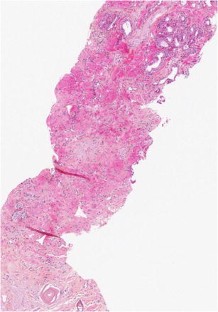

Low-risk prostate adenocarcinoma is classically managed either with active surveillance or radical therapy (such as external radiotherapy or radical prostatectomy), but both have significant side effects. Vascular-targeted photodynamic therapy (VTP) is a focal therapy proposed as an alternative approach for localized, low-volume, and low-Gleason score (≤6) carcinomas. We report histological modifications observed in prostate biopsies of 56 patients, performed 6 months after VTP using the photosensitizer TOOKAD® Soluble (WST11) and low-energy laser administered in the tumor area transperineally by optic fibers. In 53 patients, we observed sharply demarcated hyaline fibrotic scars, with or without rare atrophic glands, sometimes reduced to corpora amylacea surrounded by giant multinuclear macrophages. Mild chronic inflammation, hemosiderin, and coagulative necrosis were also observed. When residual cancer was present in a treated lobe (17 patients), it was always located outside the scar, most often close to the prostate capsule, and it showed no therapy-related modification. Histopathological interpretation of post-WST11 VTP prostate biopsies was straightforward, in contrast with that of prostate biopsies after radio or hormonal therapy, which introduces lesions difficult to interpret. VTP resulted in complete ablation of cancer in the targeted area.